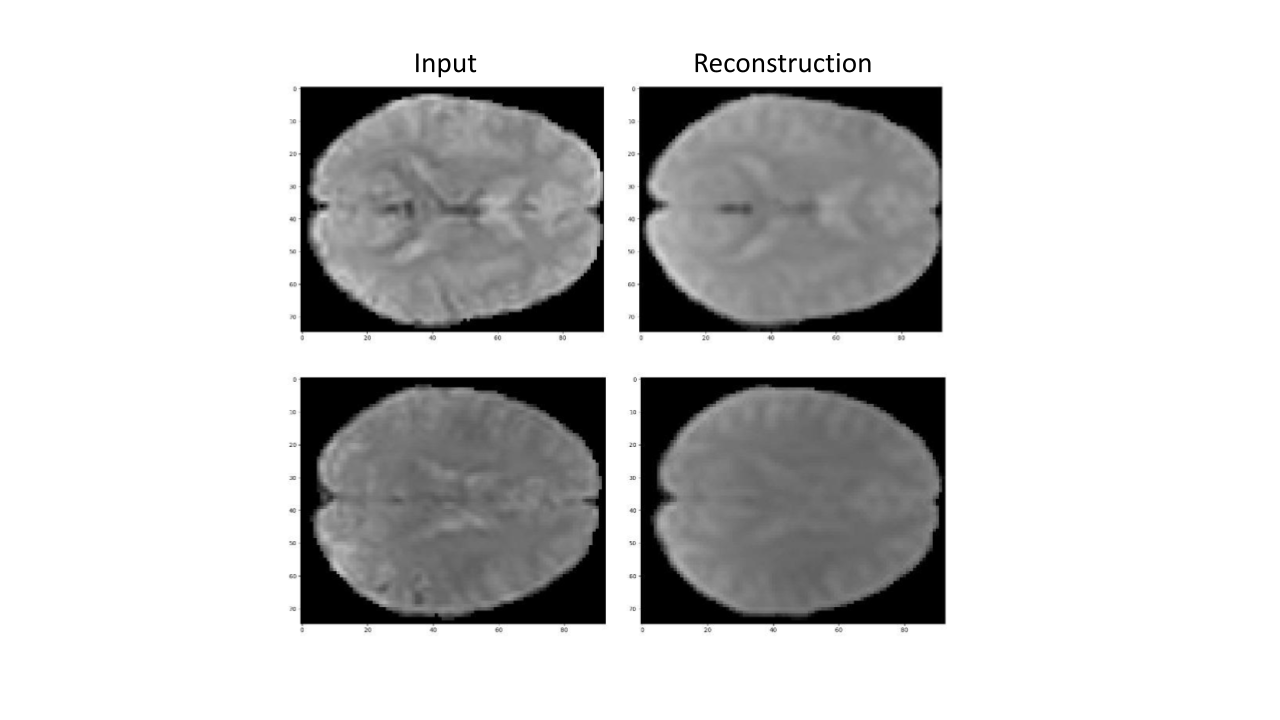

blackFig. 5 presents two slices fron two representative fMRI scans (from the validation set) that were encoded and decoded by the pre-trained TFF model. As can be seen, TFF is able to preserve most of the information from the input, including the brighter areas which indicate a higher level of brain activity. This ability of the model to accurately reconstruct the volumes is an important indication for the quality of the intermediate vectors, and the sanity of the end-to-end training.

Figure 5: \textcolorblackTwo Representative slices taken from two different subjects, along with their corresponding reconstruction created by the pre-trained TFF model. The slices were arbitrarily chosen from each subject (at depths 48 and 51 respectively).